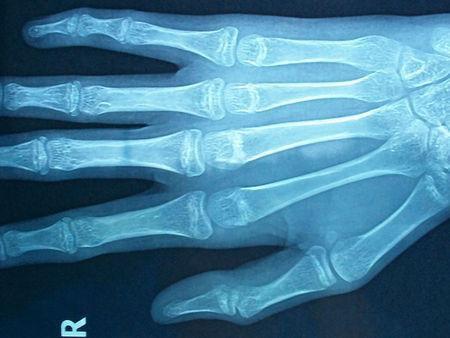

骨骺线什么时候闭合?

男性骨骺线闭合的时间大多数时间是18岁,个别最晚的是19~20岁;

骨骺线什么时候闭合

女性一般比男性早1~2岁,一般是在16-18岁左右的。

一般情况下,骨骺线闭合后就预示着人们身高基本停止增长,但是也不一定没有增高的可能,只要通过科学方法就仍然有长高机会。